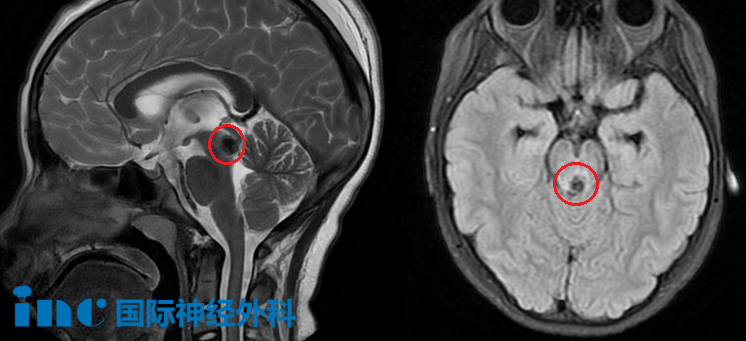

再輾轉(zhuǎn)多家醫(yī)院后,最終診斷為:中腦導(dǎo)水管區(qū)占位,海綿狀血管畸形并靜脈畸形?幕上腦積水并室旁水腫。

MRI影像

而這一次,教授明確表示:“現(xiàn)在的情況已經(jīng)與3月的截然不同,出血量超過了1厘米范圍,而且出血已經(jīng)深入腦干,進(jìn)入了中腦。我建議他們選擇手術(shù)治療,因?yàn)殡S著出血量越來越多,她會出現(xiàn)更嚴(yán)重的神經(jīng)功能問題,比如復(fù)視等。因此,現(xiàn)在是一個很好的手術(shù)時機(jī)。”

影像